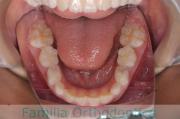

上の前歯の並びが気になるのできれいにしたい、ということで来院されました。マウスピース型矯正装置のひとつ、インビザライン/InvisalignR(薬機法および医薬品副作用被害救済制度の対象外)を用いて治療しました。

非抜歯で2年弱、20回程度の通院で治療が完了しました。

マウスピース矯正は、患者さんの協力に治療結果が左右されるところはリスクと言えるかもしれません。